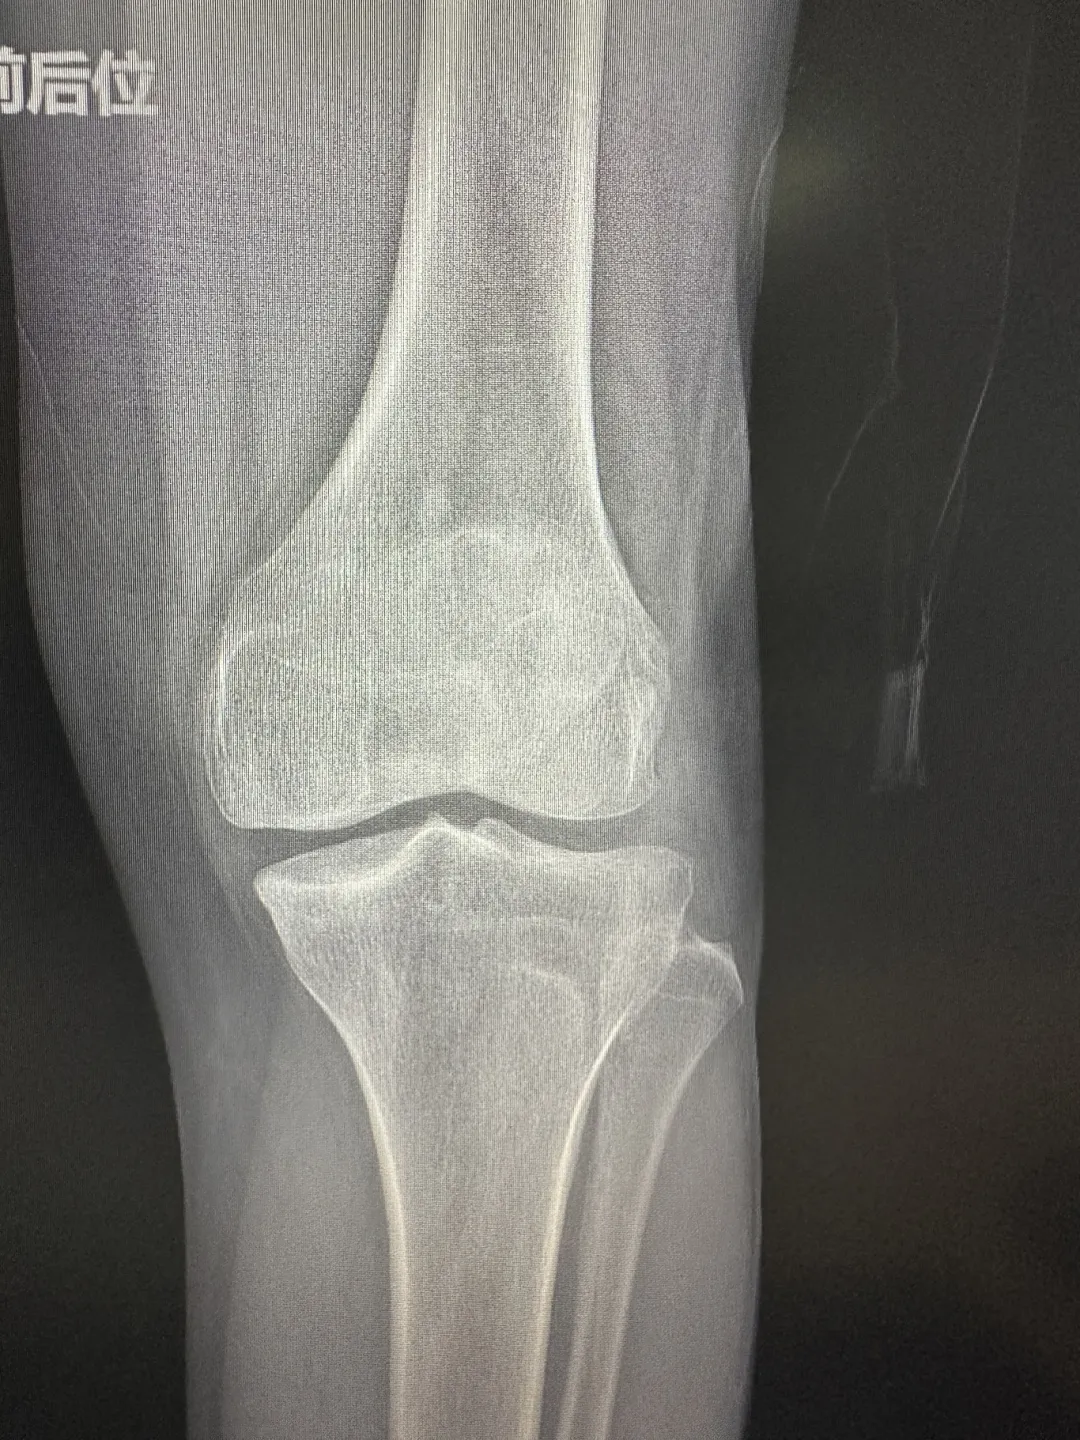

患者术前膝关节情况